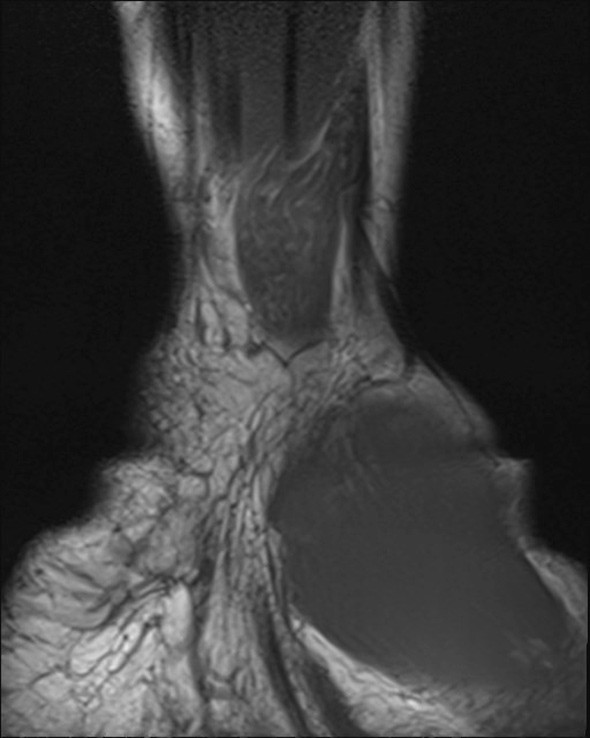

En tidligere frisk jente i tenårene ble henvist til håndkirurgisk avdeling med en kul på bøyesiden ved venstre håndledd. Denne var blitt oppdaget av mor rundt syv år tidligere og var etter hvert blitt økende smertefull. Pasienten beskrev overfølsomhet for berøring og nummenhet i tommel, peke-, lang- og ringfinger. Perkusjon over tumor ga utstrålende smerter og økt nummenhet i de samme fingrene. MR-undersøkelse viste en fortykket medianusnerve med utseende som en kabel på grunn av fibrøs fortykkelse av peri- og endonevrium og økt mengde fett som separerer de ca. 15 nerveaksonene (bilder på nett). Tumorens utbredelse var ca. 10 cm. Tilstanden ble diagnostisert som et lipofibromatøst hamartom på grunn av MR-funnene, som angis som patognomoniske for tilstanden (1).

Det ble gjort eksplorasjon av tumor og dekompresjon av nerven i karpaltunnelen. Bildet viser tumoren, som på det tykkeste hadde 3 × større diameter enn en normal nerve. Ved kontroll to og seks måneder senere hadde pasienten de samme smerteplagene som før operasjonen, men følesansen i fingrene var forbedret. Nevrografi etter to måneder viste moderat aksonal og demyeliniserende sensorimotorisk affeksjon av medianusnerven i håndledds- og håndrotsnivå, tydende på kompresjonsnevropati. EMG-undersøkelse viste sparsom denervasjonsaktivitet og funn som ved gjennomgått reinnervasjon. Det var ingen tidligere undersøkelser som man kunne sammenligne med.